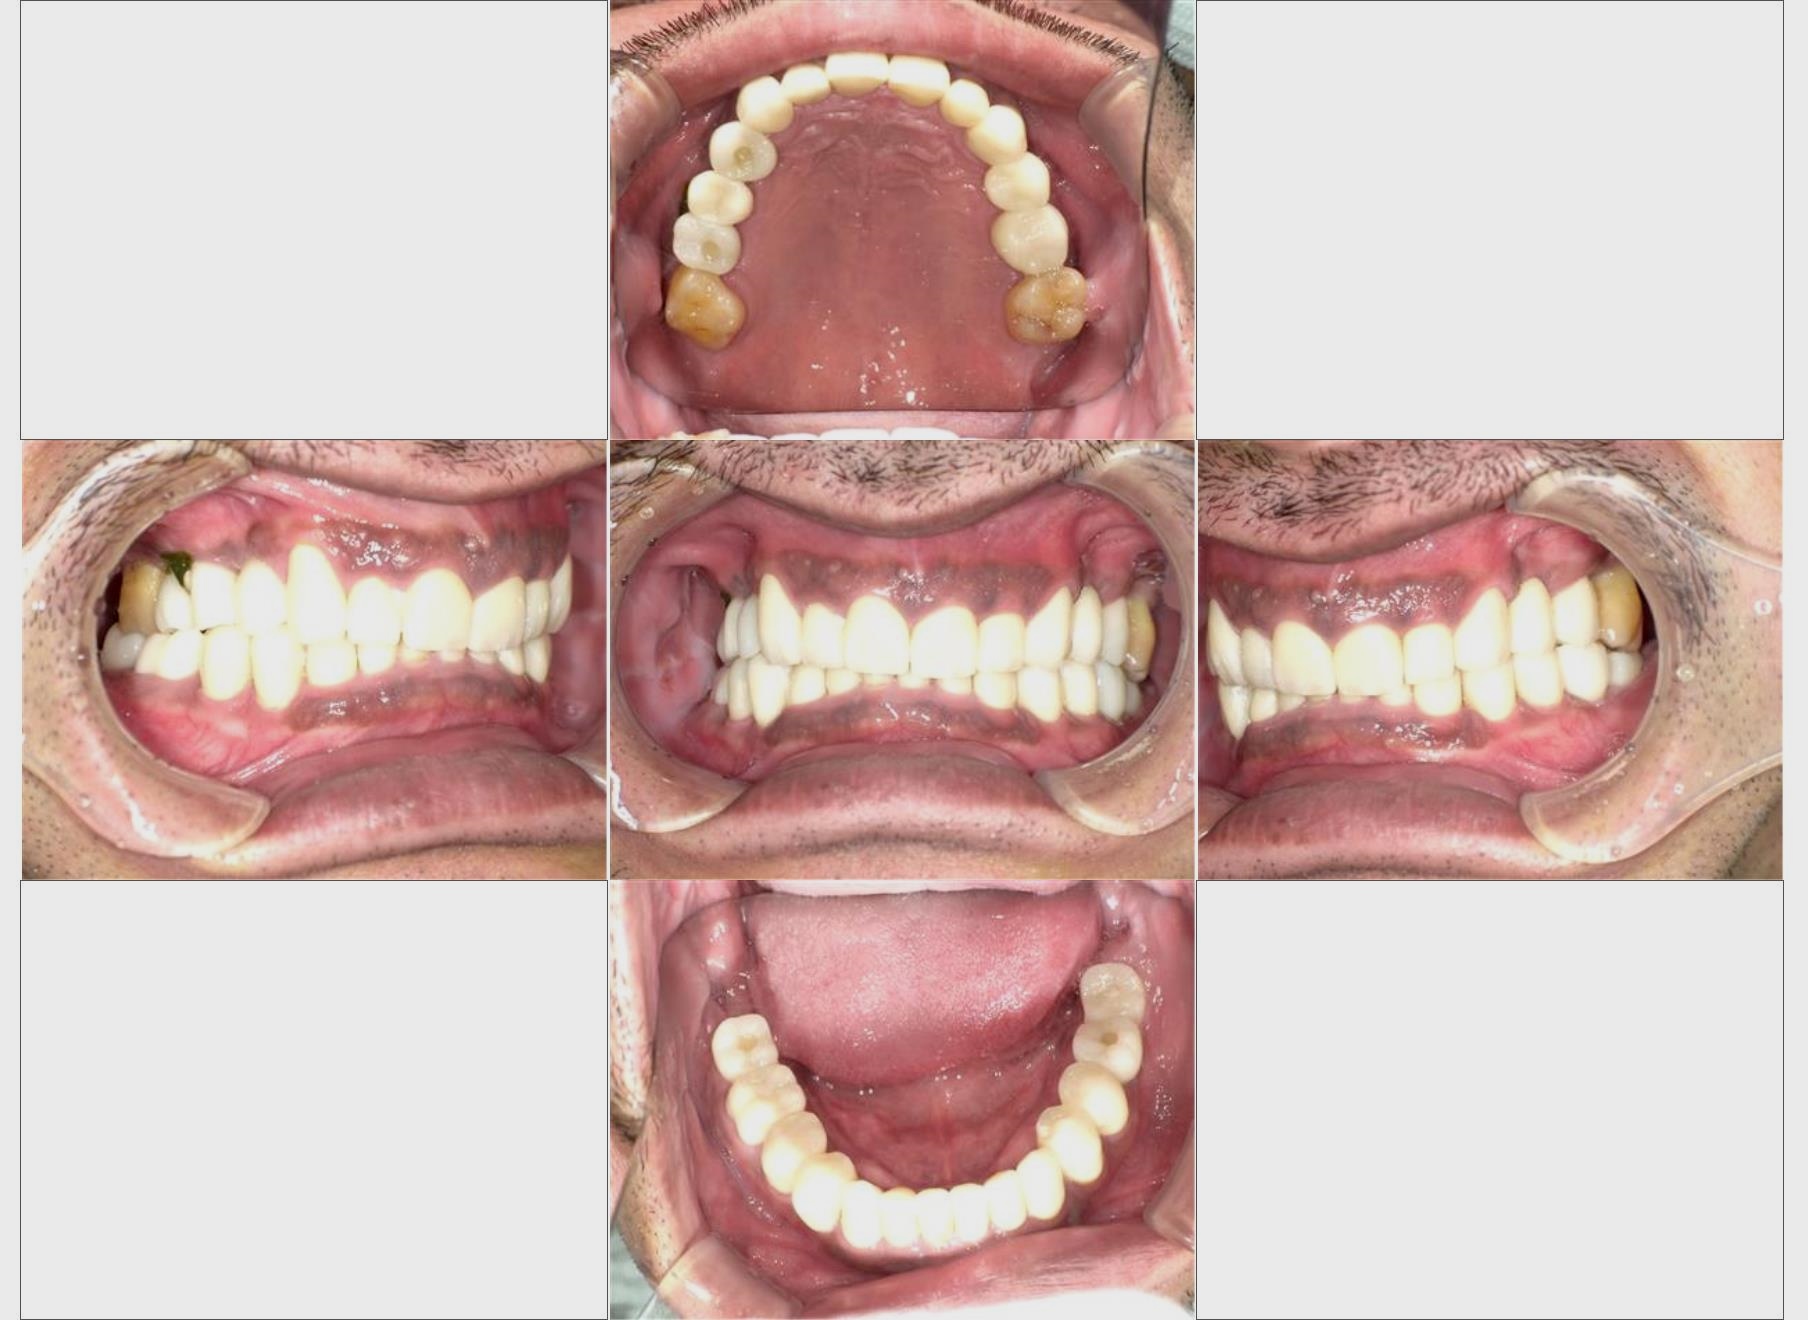

インプラント治療

40歳/男性

Before

After

- 期間/回数

- 4ヶ月半/7回

- 費用総額

- 2,530,000円円(税込)

(副作用・リスク) インプラント歯周病 インプラント周囲炎症